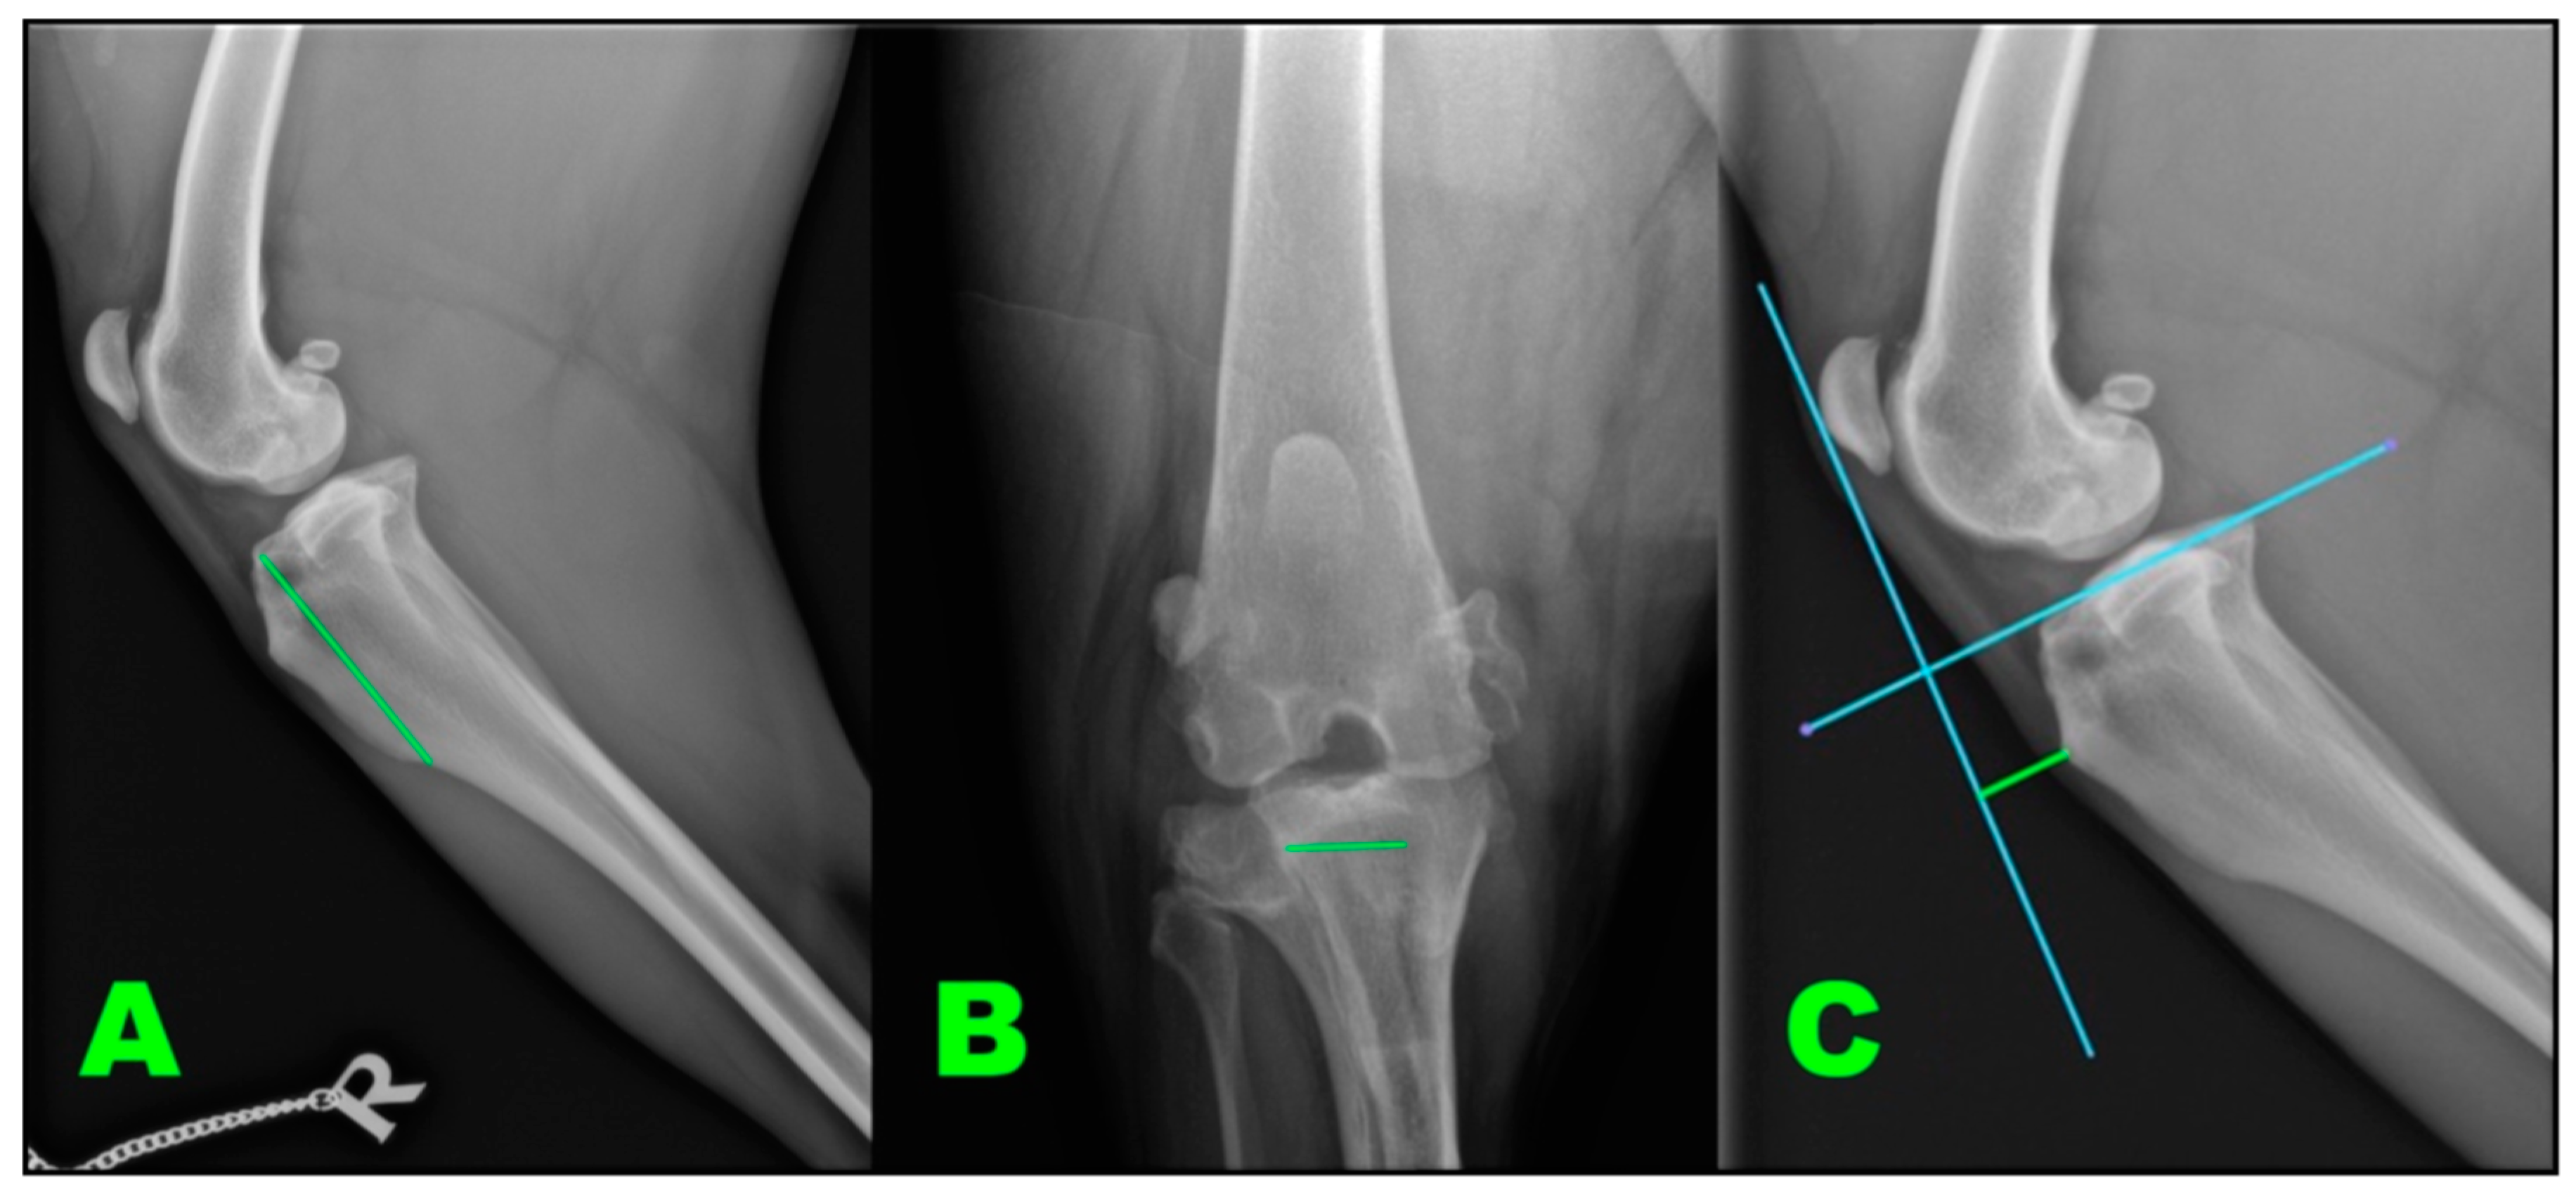

2.2.4. Radiographic Assessment

- Millet, M.; Bismuth, C.; Labrunie, A.; Marin, B.; Filleur, A.; Pillard, P.; Sonet, J.; Cachon, T.; Etchepareborde, S. Measurement of the patellar tendon-tibial plateau angle and tuberosity advancement in dogs with cranial cruciate ligament rupture: Reliability of the common tangent and tibial plateau methods of measurement. Vet. Comp. Orthop. Traumatol. 2013, 26, 469–478. [Google Scholar] [CrossRef] [PubMed]

- Etchepareborde, S.; Brunel, L.; Bollen, G.; Balligand, M. Preliminary experience of a modified maquet technique for repair of cranial cruciate ligament rupture in dogs. Vet. Comp. Orthop. Traumatol. 2011, 24, 223–227. [Google Scholar] [CrossRef]